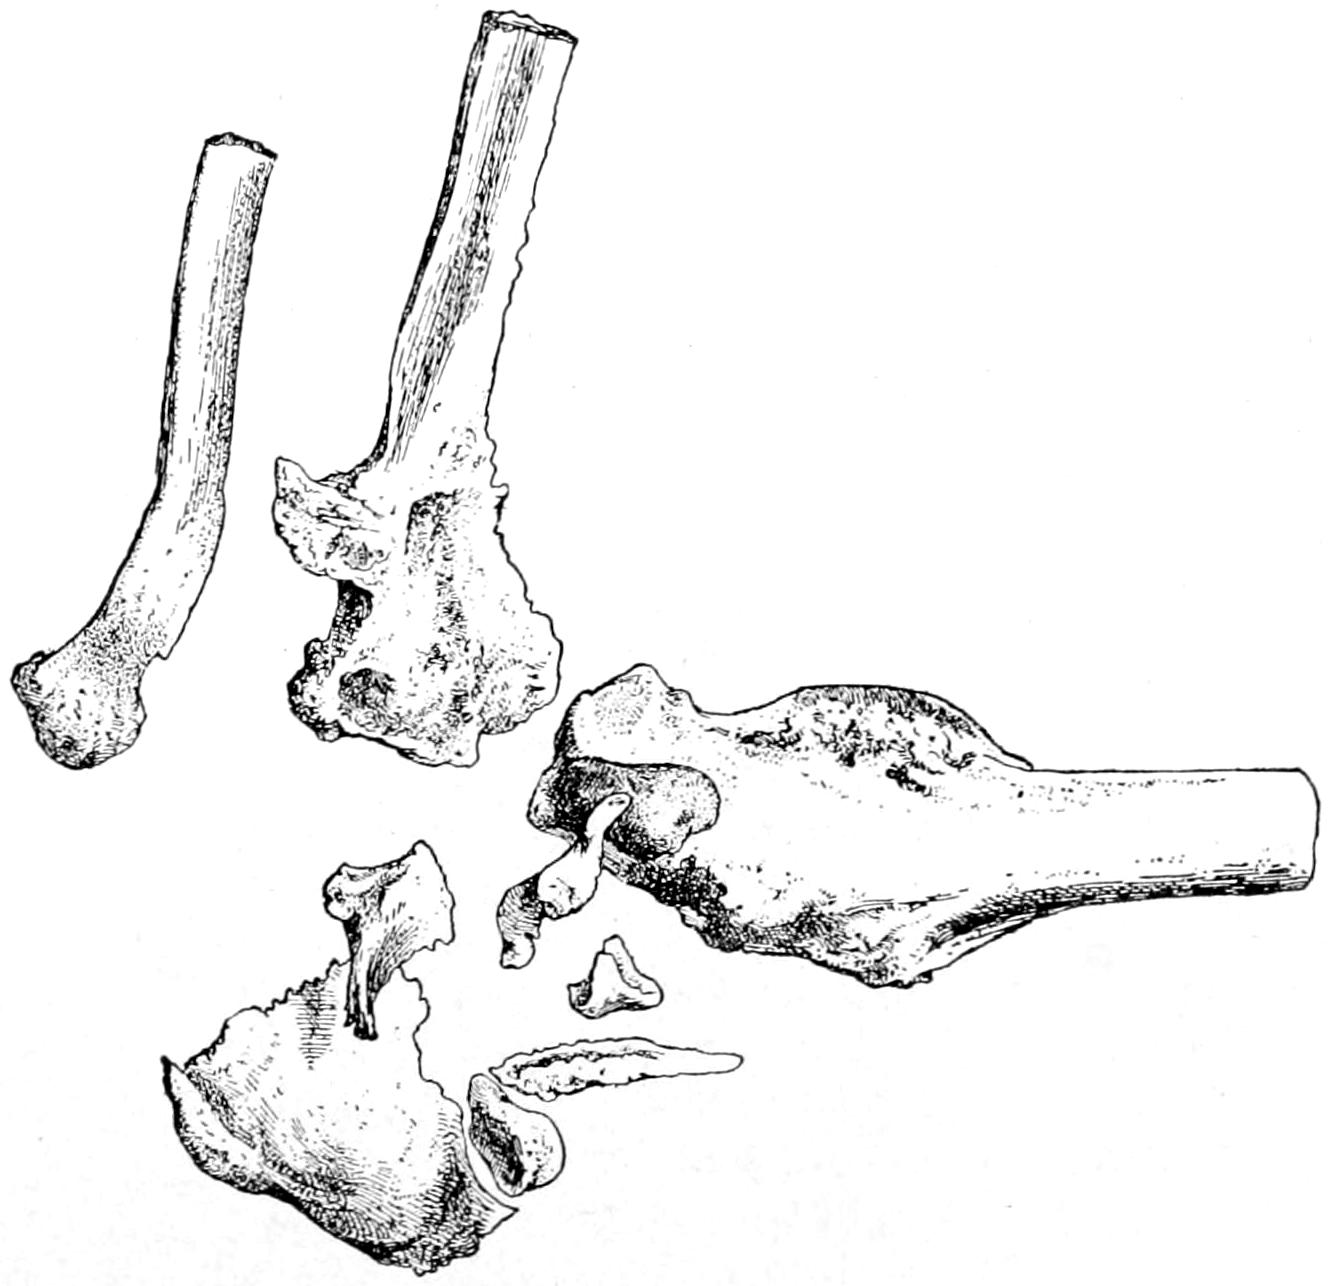

Fig. 1

Congenital hypertrophy: gigantism of both lower extremities. (Case of Dr. Graefe [Sandusky].)